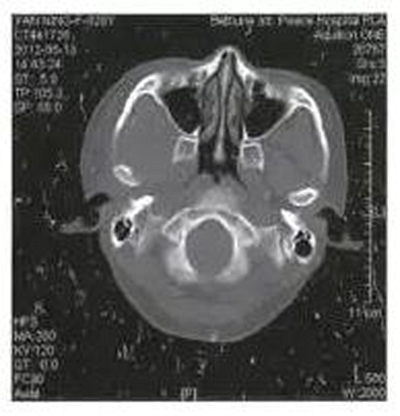

病例1,男,26歲。1月前在當(dāng)?shù)劓?zhèn)醫(yī)院拔除左上頜第三磨牙,術(shù)后3天出現(xiàn)左側(cè)面部腫脹,疼痛,張口受限,張口度約20mm,在當(dāng)?shù)剡M(jìn)行全身抗生素治療,局部未予任何處理,效果不佳。CT示左側(cè)咬肌間隙及顳下間隙腫脹,左側(cè)髁突頸部骨質(zhì)破壞,明顯死骨形成(圖1)。

圖1左側(cè)髁突骨髓炎,死骨形成

收入院后全麻下經(jīng)耳前顳部手術(shù)入路暴露病變區(qū)域,術(shù)中見(jiàn)左側(cè)髁突頸部外側(cè)骨皮質(zhì)破損,死骨分離。術(shù)中刮除死骨,貫通各個(gè)膿腔,引流膿液,放置引流條,抗感染治療,術(shù)后1月張口度恢復(fù)正常。